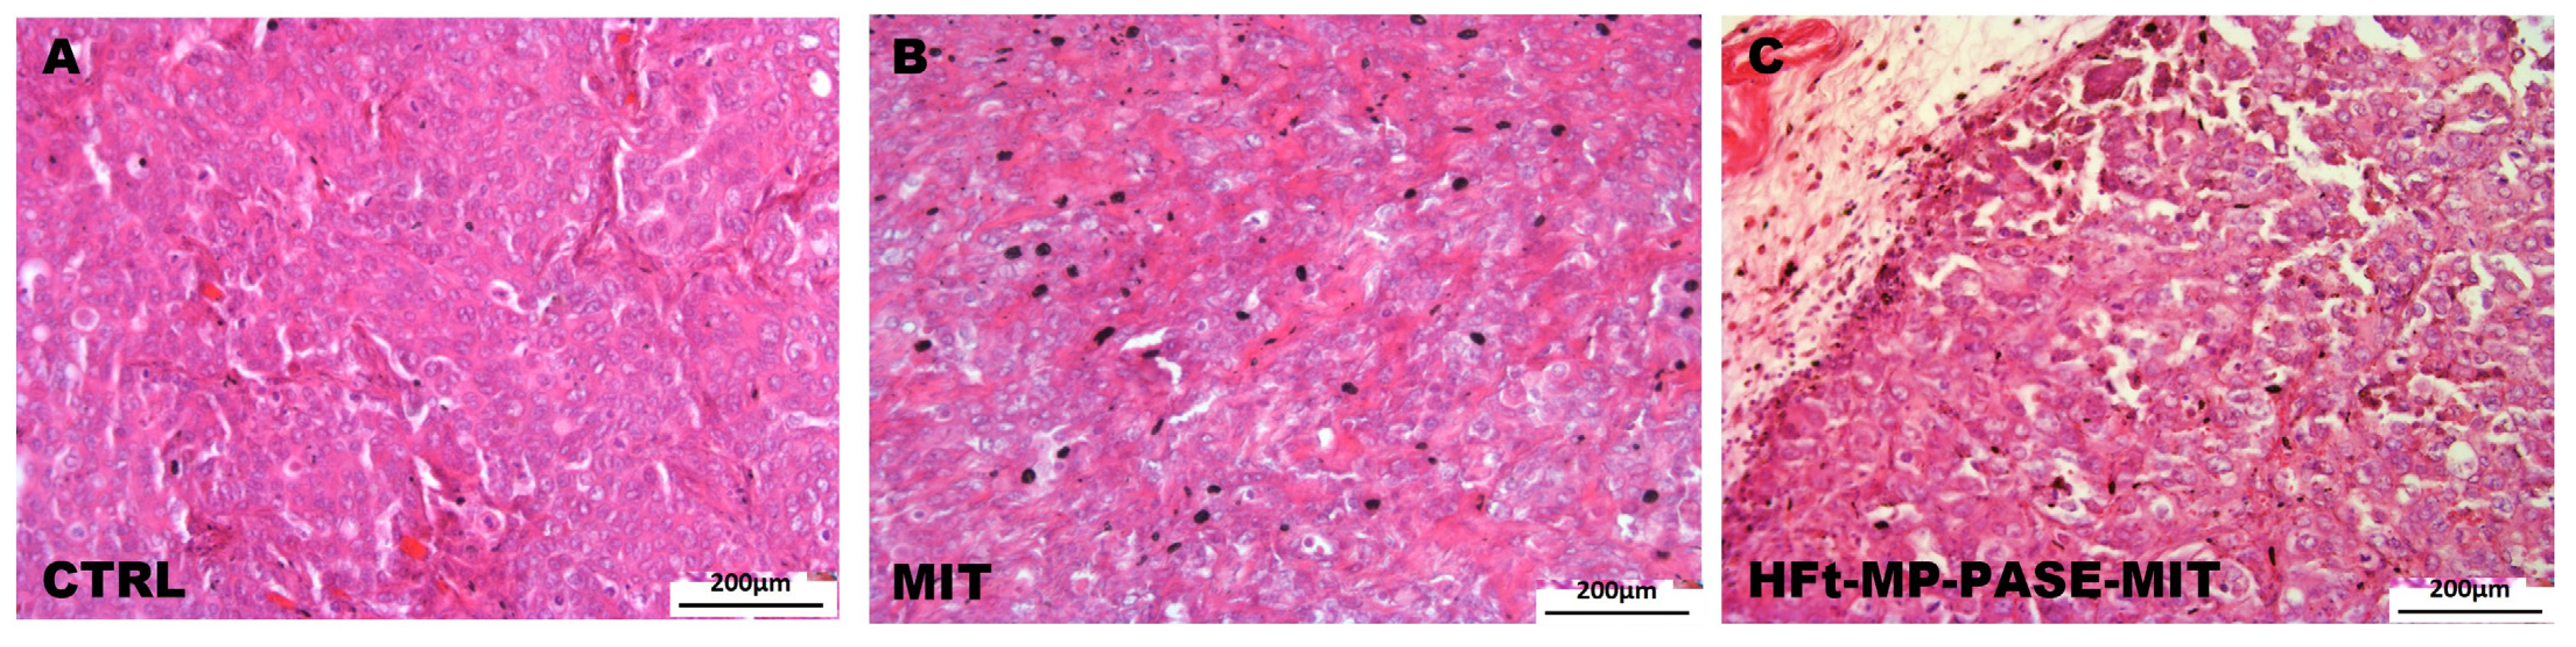

Histological evaluation of parenchyma primary tumor mass was performed using hematoxylin and eosin stain to verify the treatment efficacy of HFt-MP-PASE-MIT nanosystem. In fact as depicted in Figure 5A, tumor explanted from a representative mouse belonging to the control group showed very dense parenchyma morphology typical of pancreatic tumors with the presence of numerous capillaries. While the representative tumor, explanted from mouse belonging to the group treated with HFt-MP-PASE-MIT, showed numerous necrosis areas and scarce vascularization (Figure 5C). The treatment with free MIT, representing a non-targeted drug, is less efficient in reducing primary tumor viability (Figure 5B). Indeed, MIT administration showed a dense structure of primary tumor with rare areas of necrosis and a good presence of capillaries. Similar histological tumor mass profiles were screened for each group treatment and the selected images display representative morphologies.

Figure 5.

Histology of primary tumor mass. Images show the parenchyma of primary tumors in all the experimental groups. (A) A representative image of primary tumor mass collected from the control group treated with saline; (B) mice treated with free MIT; (C) mice treated with HFt-MP-PASE-MIT.